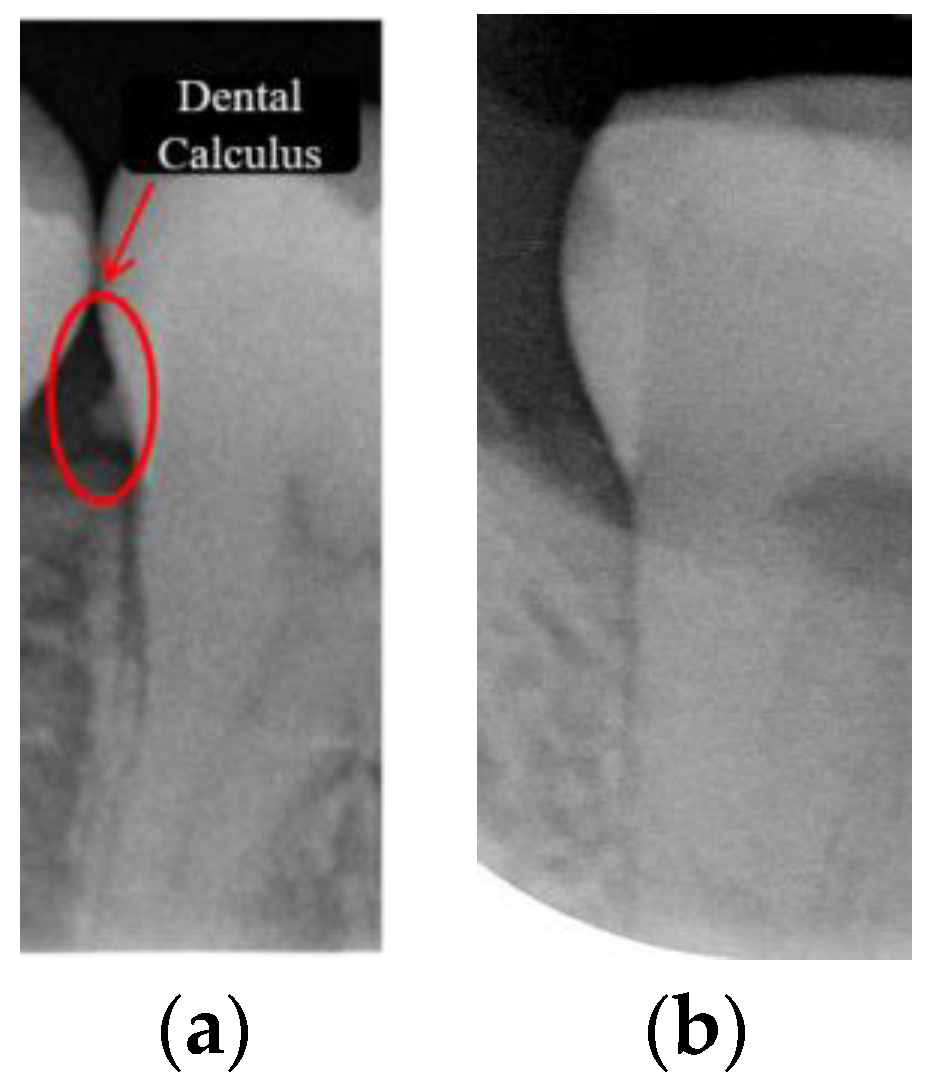

Dental calculus is recognized as a mineralized biofilm that comprises diverse calcium phosphate crystals, which may accumulate on the root surface both supra- and subgingivally [5]. A positive correlation between calculus deposits and periodontitis has been confirmed in multiple studies [6,7]. Despite clear evidence that the surface roughness of calculus alone does not initiate gingivitis, it is important to emphasize that calculus is consistently covered by an unmineralized layer of a viable biofilm [8], which is a primary factor in gingival inflammation [9]. The characteristics of dental calculus are not obvious in a BW image, as shown in Figure 1. The mechanical removal of subgingival plaque and calculus stands as the gold standard in the treatment of periodontitis [10]. While supragingival calculus can easily be seen and removed through sonic/ultrasonic instruments, subgingival calculus is invisible during intra-oral examination. Therefore, the identification of subgingival calculus is critical for the diagnostic process. Radiographic images have been widely used across various applications in the dental field [11]. Subgingival calculus is generally detected during periodontal probing, while radiographic examination can only show calculus on the proximal surfaces [12,13]. Meanwhile, Buchanan et al. [14] reported that the detection of dental calculus on the root surface by radiography had shown low sensitivity but high specificity, and a manual diagnosis can only detect dental calculus in 44% of the 275 datasets that truly have the condition. The detection ability can be increased to 82.2% by staining teeth with 1% methylene blue [15]. Galal et al. [16] observed that periapical films and intra-oral surveys showed comparable efficacy in calculus detection, with a particularly significant enhancement in detection when supplemented with radiographs. In comparison, other dental conditions like caries and periodontal disease have higher detection rates with manual methods. The detection rate for caries is approximately 70–85%, and for periodontal disease, it is around 65–80% [1]. Subgingival calculus documentation is crucial for periodontal assessment. Although clinical assessments are more common for detecting calculus, utilizing BW radiographs offers several advantages in calculus assessment. Firstly, BW images provide a comprehensive view of the tooth structure, allowing for a more thorough examination of interdental spaces where calculus often accumulates. Additionally, BW radiographs enable dentists to visualize areas that may be difficult to access during a clinical examination such as posterior regions. This enhanced visualization can aid in the early detection of calculus, leading to timely interventions and improved patient outcomes.

Figure 1.

Dental calculus symptoms on a BW image: (a) dental calculus symptoms; (b) absence of dental calculus symptoms.